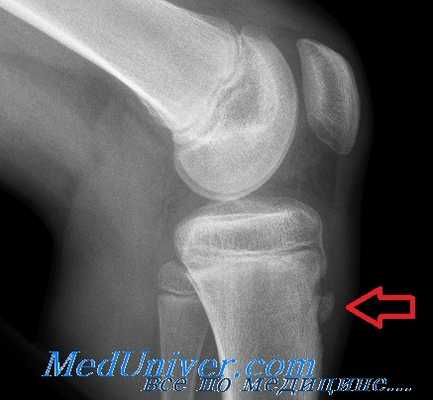

Рентгенологически отмечается характерная картина для этого заболевания. У молодых людей, когда еще не закрылась зона роста, видны неслившийся апофиз бугристости и отдельные костные фрагменты. Часто можно видеть значительную деформацию бугристости в виде «хобота». У более старших танцовщиков эта бугристость может иметь вид отдельных костных фрагментов.

Основным методом инструментальной диагностики является рентген коленных суставов в двух проекциях, который позволяет увидеть структурные изменения бугристости [4] .

Фрагментацию с отрывом костного фрагмента лучше всего видно на боковой рентгенограмме [10] .